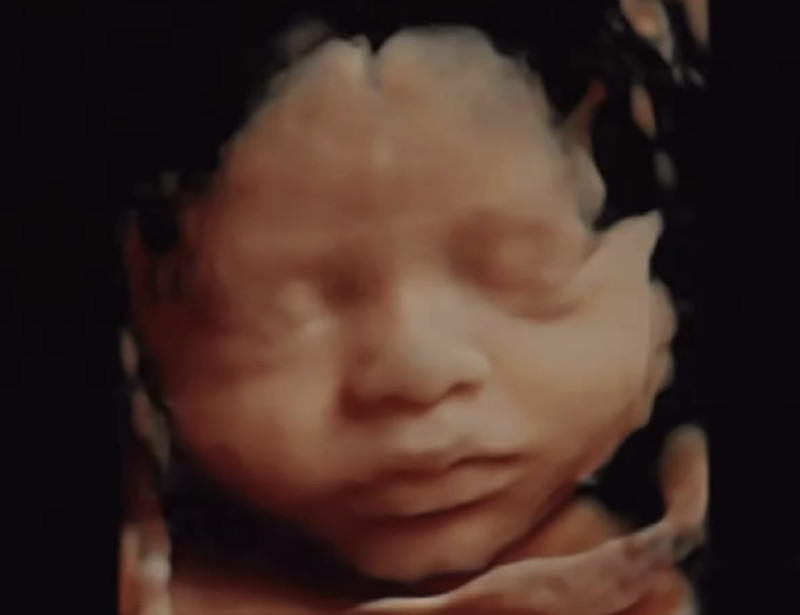

You can decide for yourself. The striking before-and-after comparison below highlights the accuracy of 3D/4D ultrasound imaging by showcasing a detailed image of a fetus alongside a photograph of the infant after birth. The lifelike representation provided by 3D/4D technology enhances prenatal bonding, allowing parents to connect with their child even before delivery. This juxtaposition underscores the advancements in imaging that make prenatal diagnostics more engaging and emotionally impactful.